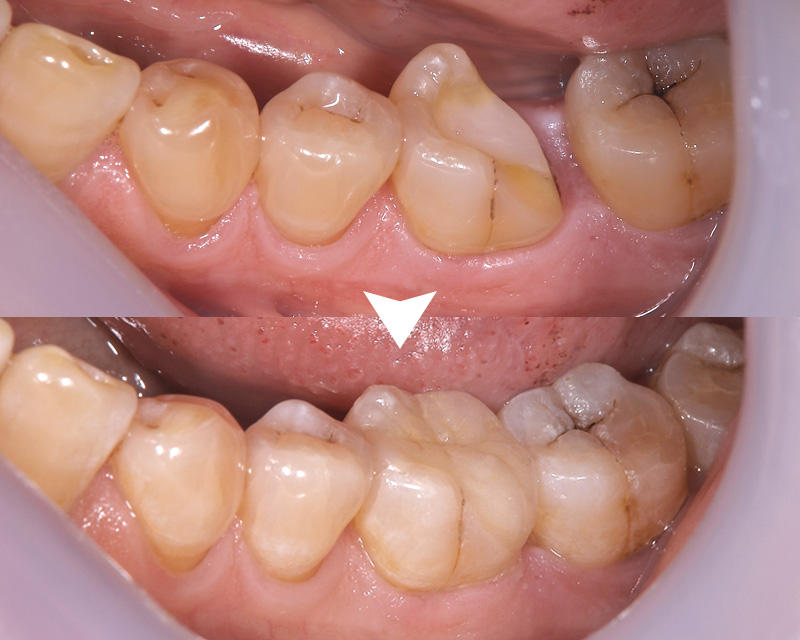

歯と強固に接着できる → 【メリット】虫歯が再発しにくい

金属の詰めものは虫歯の再発を起こしやすいです。理由は接着剤が劣化しやすく、接着がはがれた歯と金属の隙間から虫歯菌が侵入するためです。

セラミックは歯と化学的に接着させることが可能なので、隙間から虫歯が再発するリスクを最小限に抑えることが可能です。

時間が経っても劣化しない → 【メリット】きれいな状態が長期に維持される

プラスチックの詰めものは最初はきれいですが、吸水性があるので長期的には劣化していきます。劣化すると着色したり、汚れがつきやすくなったり、欠けやすくなります。(長期間使用したプラスチック製の食器と、ガラスや陶器を比較してイメージしてもらうとわかりやすいかもしれません)

セラミックは時間が経っても劣化しないので、きれいな状態が長期に維持されます。